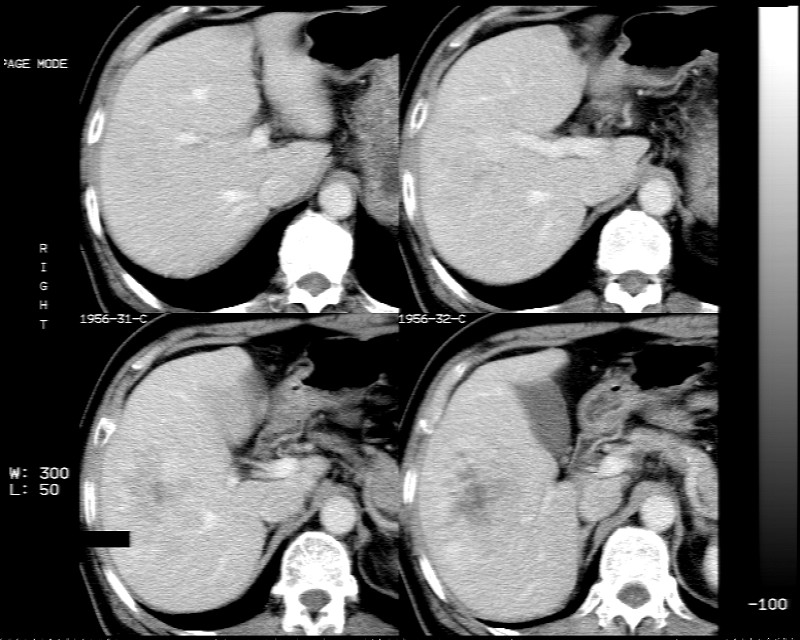

肝右叶巨大占位性病变,平扫呈低密度改变,增强扫描动脉期病灶周围强化,门脉期强化未退出,延时期病灶周边强化与肝实质接近,病灶中心在各期均可见星状不强化区;首先考虑局灶性结节增生可能性大,其次为血管瘤。肝癌不能完全排外(不首先考虑肝癌是因为强化不支持快进快出特点)。

支持局灶性结节增生。延迟期中央低密度影缩小,说明有强化,应为星状瘢痕组织而不坏死,应适当再延长时间扫描。

动态增强扫描示:动脉期病灶显著不均性强化,病灶强化密度高于肝实质;平衡期病灶呈等密度;延迟扫描病灶密度略低于肝实质;三期均见占位病灶内有裂隙状无强化影。肝内胆管无扩张,腹膜后未见肿大淋巴结。

拟诊:肝右后叶下段内占位性病变,考虑为肝结节样增生。

建议进一步检查(mri/或穿刺活检),不排外肝ca。